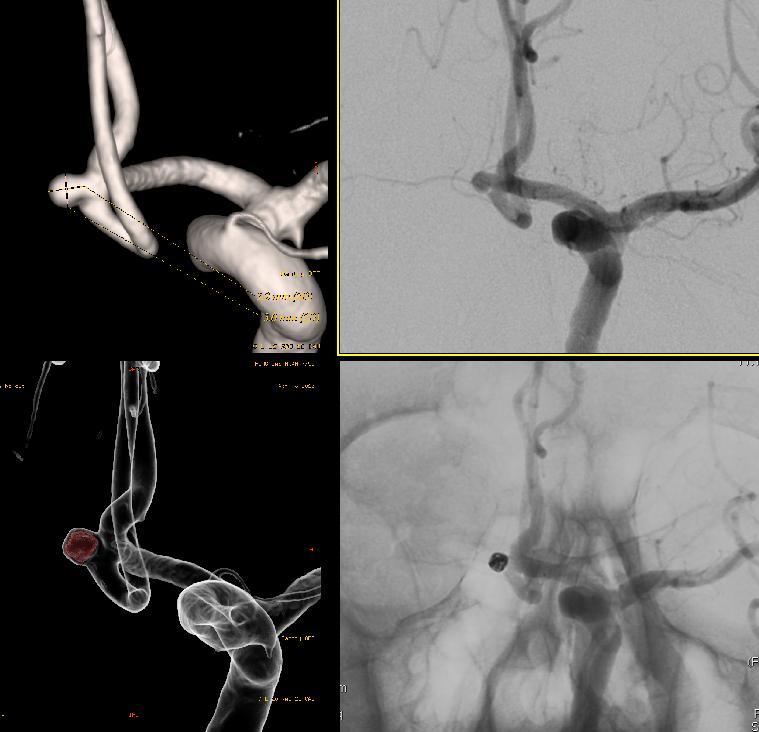

먼저 뇌혈관조영술을 통해 뇌동맥류의 정확한 현재 상태를 파악하시고 뇌동맥류 코일색전술을 하기 위한 준비를 하십니다.

미세도관을 뇌동맥류가 있는 곳에 안전하고 정확하게 초선택 하신후 뇌동맥류 크기에 맞는 프레임 코일을 선정하시어 뇌동맥류의 전체적인 프레임을 잡으시고 나머지 빈 공간에 채우는 코일을 이용하여 채우기 시작하십니다.

여러개의 채우는 코일이 들어가고 난 후 뇌혈관조영술로 확인해 본 결과 더이상 뇌동맥류에 혈류가 흐르지 않는 것을 확인하시고 시술을 종료하십니다.